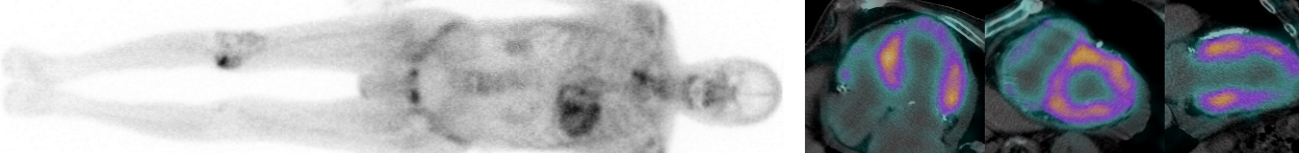

Syndrome inflammatoire chronique et insuffisance rénale aiguë chez un homme de 74 ans aux antécédents d’insuffisance cardiaque sur cardiopathie dilatée OH.TEP-TDM au 18F-FDG (difficultés d’injection du FDG a […]